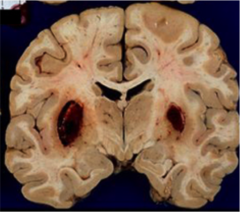

Acute hypertensive hemorrhage

Front

distribution of lenticulostriate branches of MCA perforating arterioles to the pons of basilar artery most often affects deep cerebral nuclei (putamen, thalamus, caudate nucleus)

Back